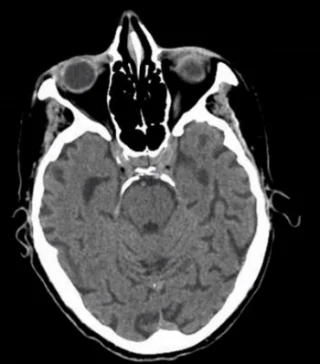

Utilizing a systematic approach is one way that the clinician can ensure significant neuropathology will not be missed.

Just as physicians are taught a uniform, consistent approach to reading an ECG (rate, rhythm, axis, etc.), the cranial CT can also be broken down into discreet entities, attention to which will help avoid the pitfall of a missed diagnosis.

One suggested method to avoid missing an emergent diagnosis is to use the mnemonic “Blood Can Be Very Bad”. In this mnemonic, the first letter of each word prompts the clinician to search a certain portion of the cranial CT for pathology: Blood = blood, Can = cisterns, Be = brain, Very = ventricles, Bad = bone.

B(lood) is for Blood

Ask yourself three questions:

Is blood present?

If so, where is it?

If present, what effect is it having?